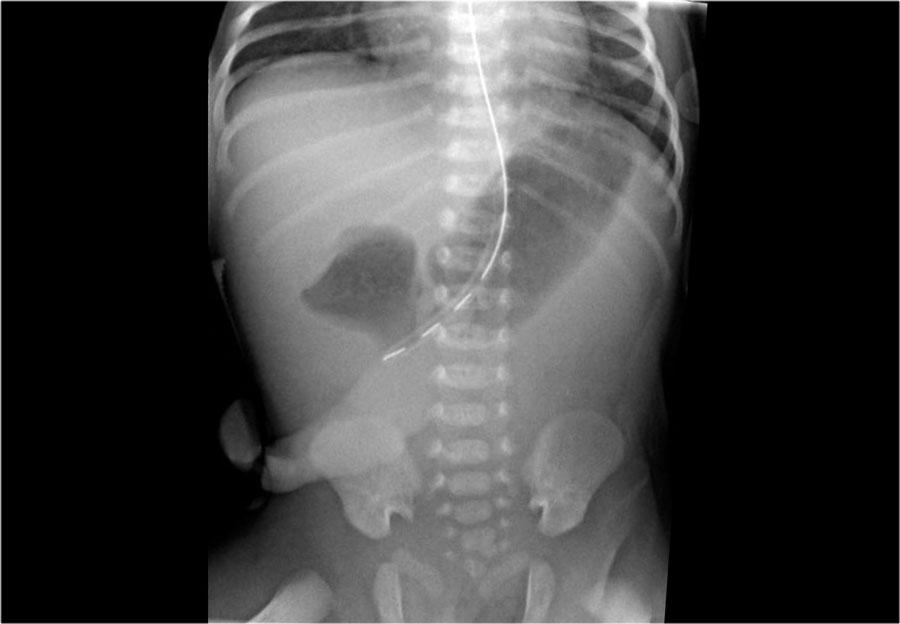

• Duodenal atresia

• Classic “double bubble” sign on X-ray

• Presents with early bilious vomiting

• Annular pancreas

• Can cause duodenal obstruction